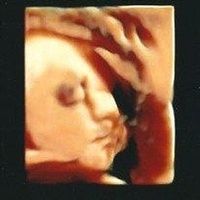

2019 - 2019Emberly Tish